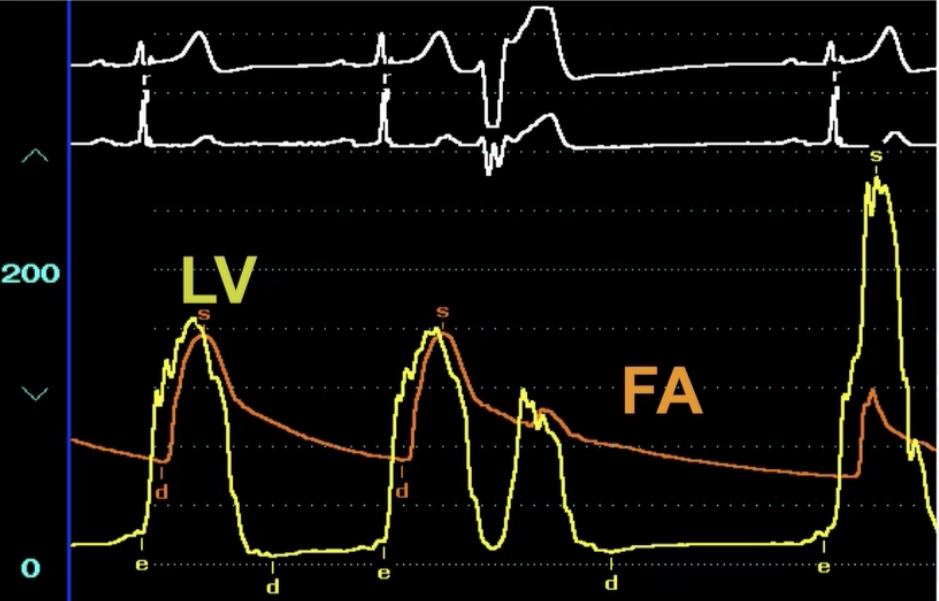

Describe the findings

HOCM - Brockenbrough sign